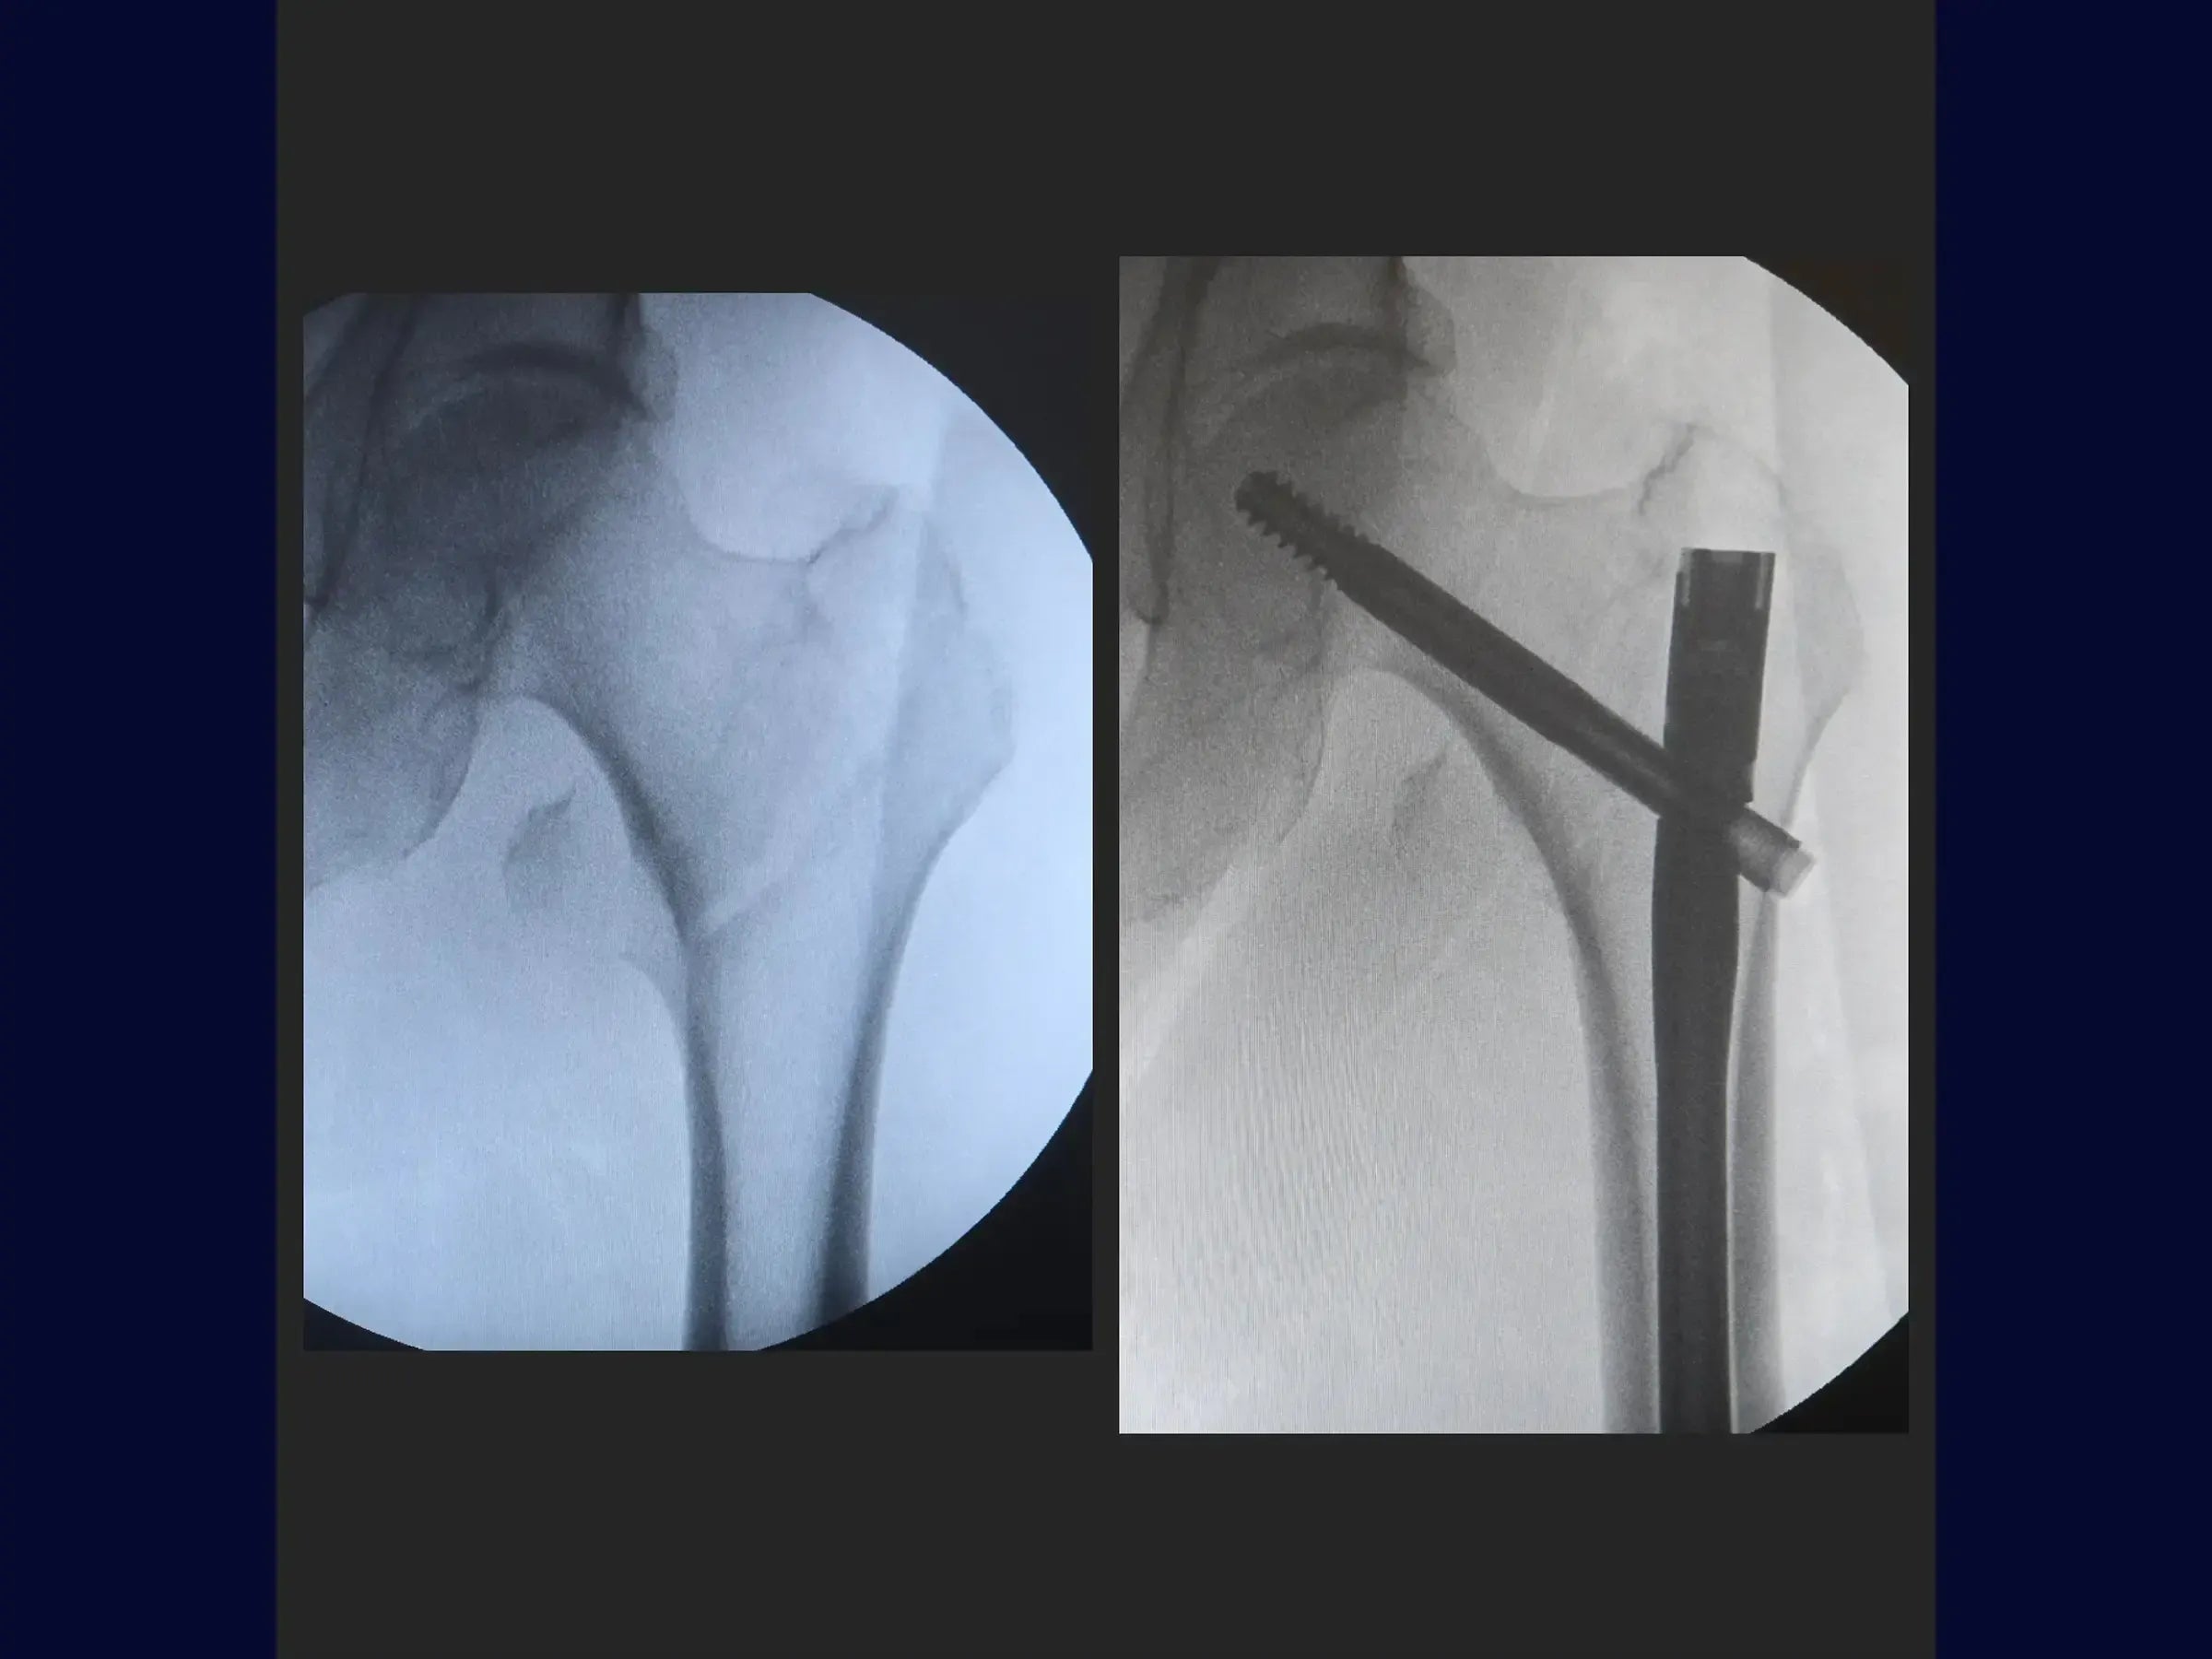

Fratura Transtrocanteriana com Haste Intramedular (Sem Mesa de Tração)

Domine o tratamento cirúrgico de fraturas transtrocanterianas do fêmur com haste intramedular, agora sem a necessidade da mesa de tração. Este treinamento oferece uma imersão prática na precisão da localização do ponto de entrada do fio guia, na otimização do posicionamento na visão lateral com um guia de paralelismo, e na técnica de fixação dos parafusos deslizantes e de bloqueio. O objetivo é proporcionar uma abordagem menos invasiva que permita apoio de carga precoce e um prognóstico favorável para o paciente idoso.

- Resultados: A fratura é reduzida anatomicamente, com o implante bem posicionado. A cirurgia minimamente invasiva permite apoio de carga precoce para o paciente idoso.